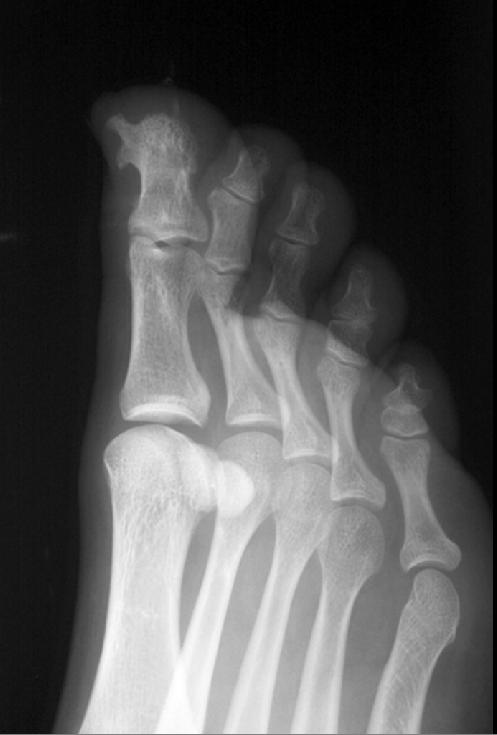

Какие будут мнения?

Приложения:

1.p7240003.jpg2.p7240004.jpg